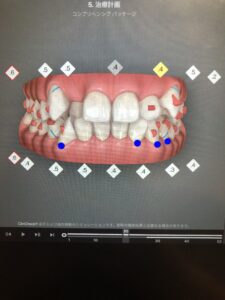

20枚目も、正面だと変化がわかりにくいですが、下から見ると隙間のある箇所が変わっているのがわかります。